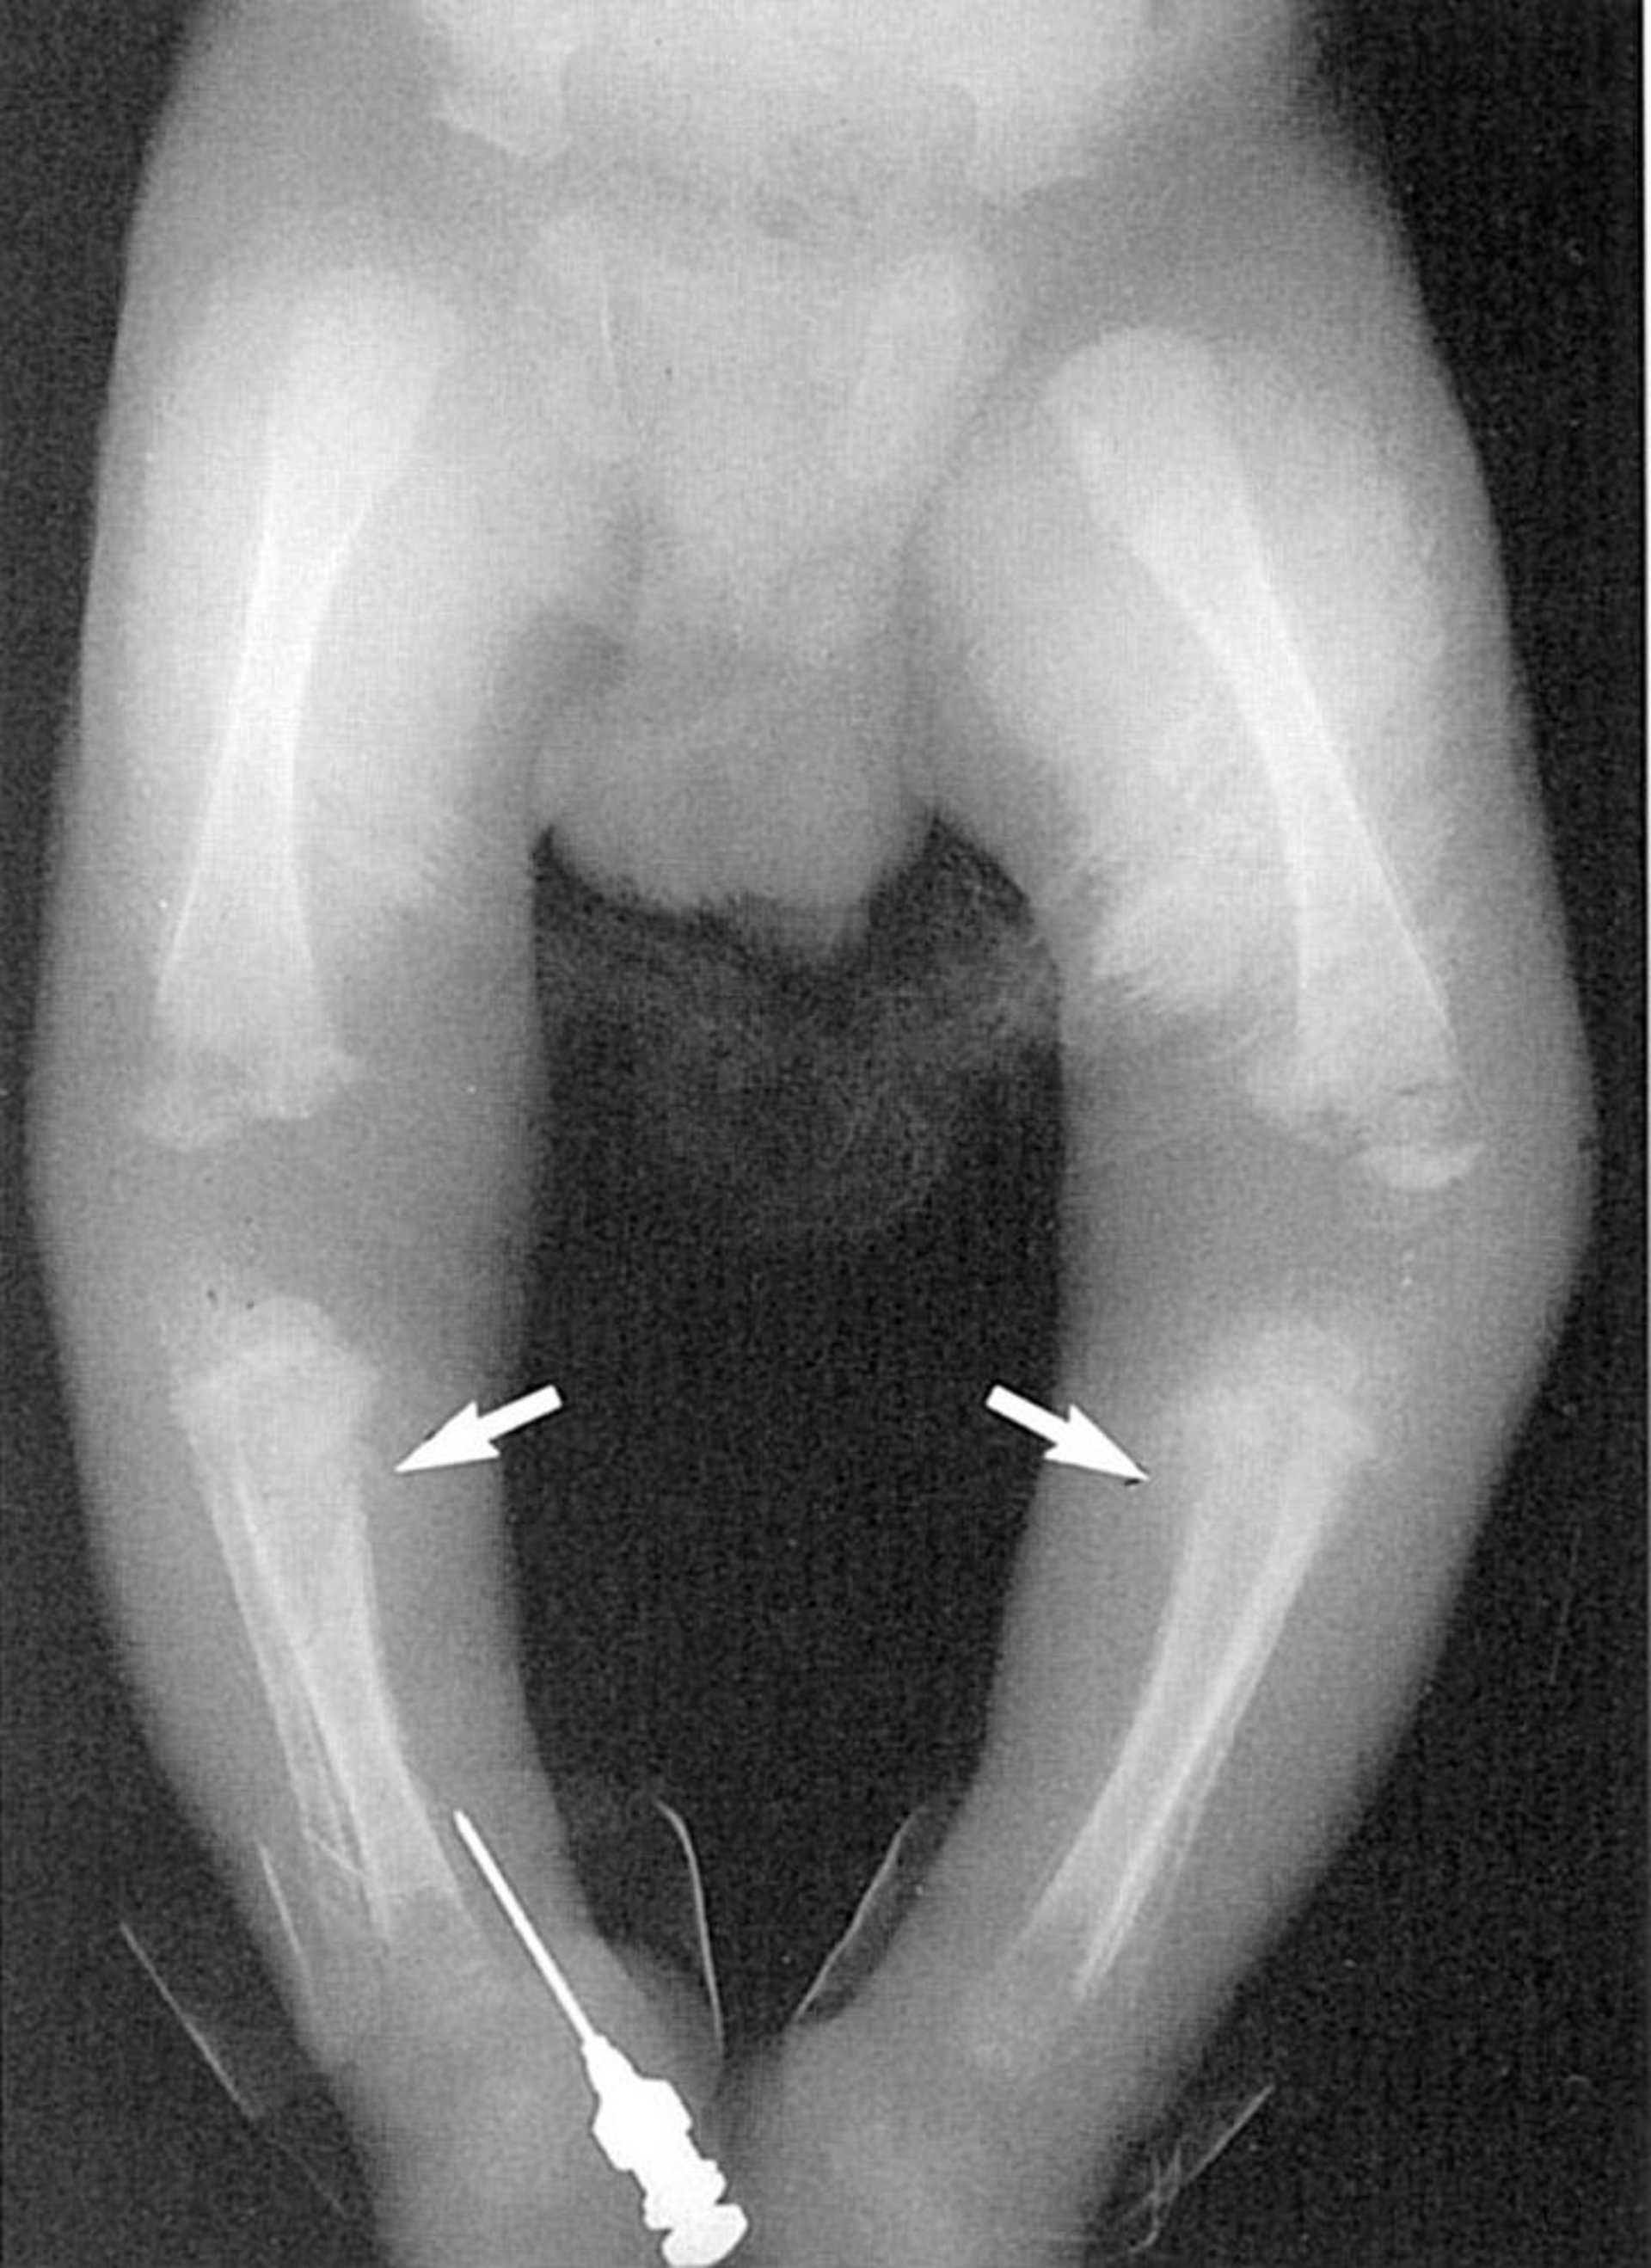

Saber Shins

Osteoperiostitis of the tibia leads to characteristic saber shins in this patient with congenital syphilis.

Image courtesy of Robert Sumpter via the Public Health Image Library of the Centers for Disease Control and Prevention.

Syphilis can cause many different abnormalities on long-bone radiographs, including

• Periosteal reactions

• Diffuse or localized osteitis

• Metaphysitis

The osteitis is sometimes described as diffuse "moth-eaten" changes of the shaft. Metaphysitis commonly appears as lucent or dense bands that can alternate to give a sandwich or celery stalk appearance. The Wimberger sign is symmetric erosions of the medial proximal tibia, but there can also be erosions in the metaphysis of other long bones. Excessive callus formation at the ends of long bones has been described. Many affected infants have more than one of these findings.